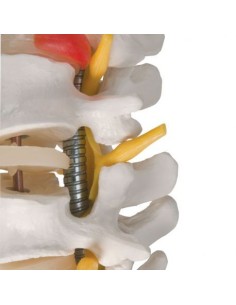

Dal cranio in 22 parti con incastri magnetici ai modelli di colonna vertebrale, da quelli di articolazioni a quelli di cuore, ogni pezzo della nostra collezione è progettato per un’immersione totale nello studio dell’anatomia umana. I nostri modelli, realizzati tramite scansioni di ossa vere, garantiscono un’esperienza tattile autentica e una fedeltà di peso quasi identica agli originali.

Essenziali per studenti e professionisti, i nostri modelli anatomici sono strumenti didattici che permettono di osservare le strutture anatomiche con precisione, eliminando la necessità di dissezioni o studi invasivi. Sono inoltre utili per spiegare ai pazienti le patologie, rendendo la comunicazione più efficace e risparmiando tempo prezioso.